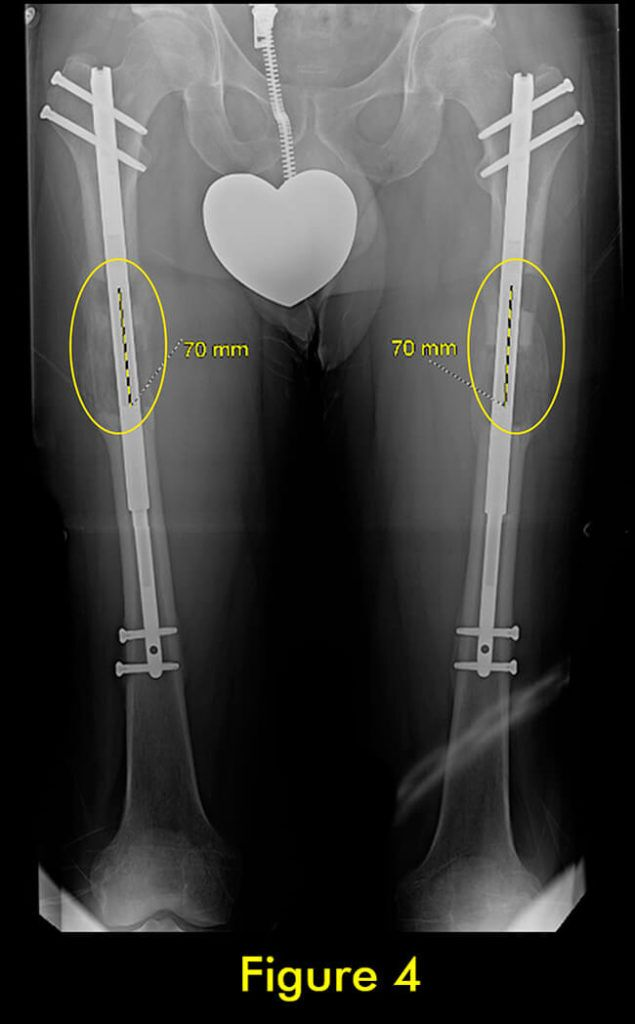

图1:延长量细微差异

图4:完全巩固